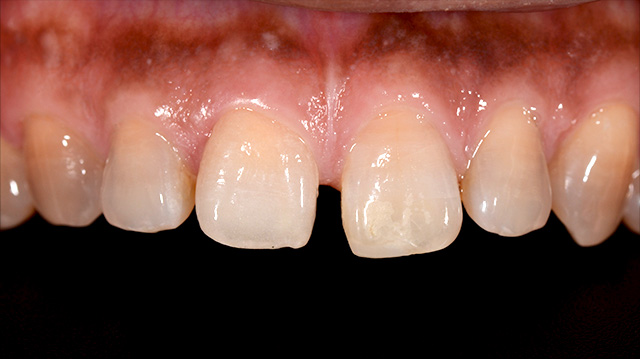

| 年代・性別 | 20代 男性 |

|---|---|

| 主訴 | 前歯の色が気になる。海外に行く前に治したい。 |

| 治療回数 | 3回 |

| 治療期間 | 約1ヶ月 |

| 費用 | 仮歯 5,500円 × 2 ジルコニアクラウン 176,000円 × 2 |